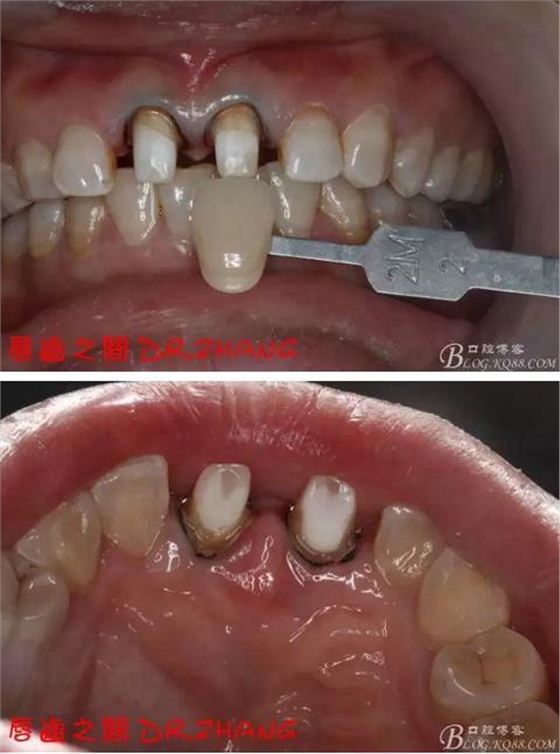

復(fù)診:臨時牙良好 患者自訴無不適癥狀 去除臨時修復(fù)體 排齦 清理牙面 試戴全瓷修復(fù)體后粘結(jié) 常規(guī)醫(yī)囑 不適隨診

總結(jié):沒有術(shù)前照片 預(yù)備牙體過長 顏色還是有差距